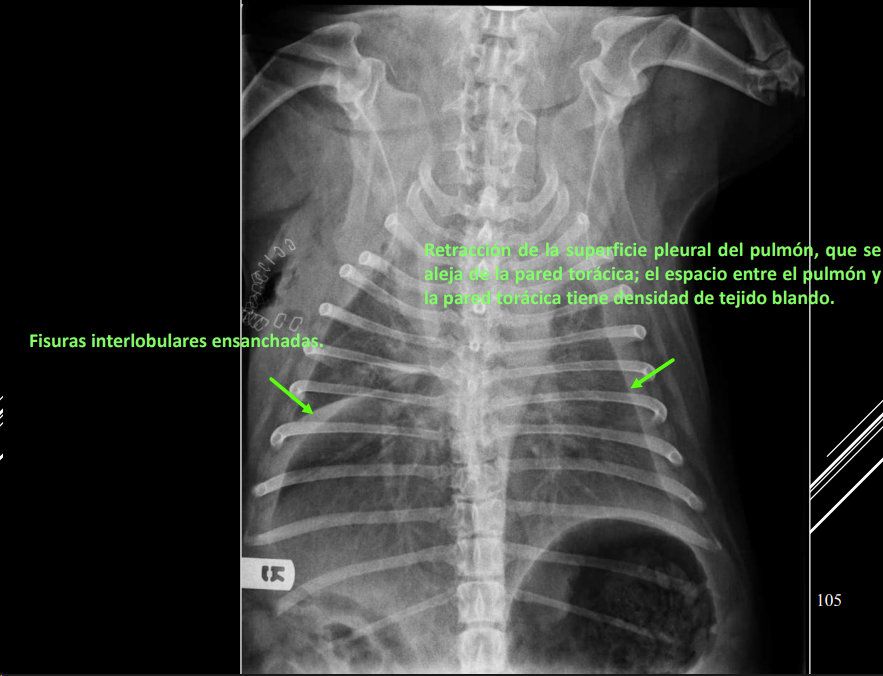

Derrame pleural

- Líquido en espacio pleural (uni/bilateral).

- RX: